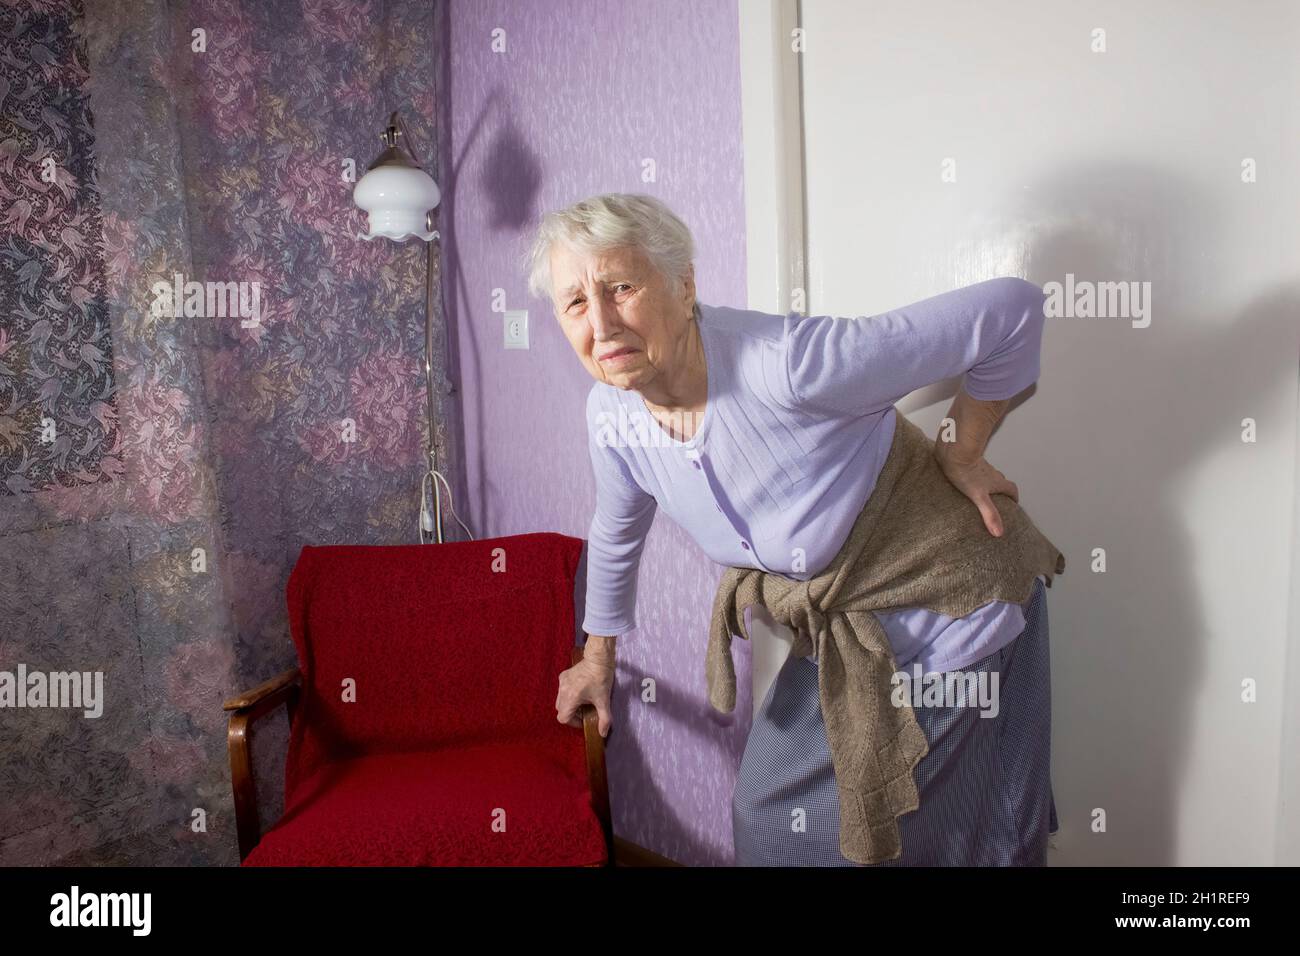

Femme âgée de 75s avec des sentiments douloureux massant bas de dos pour réduire la douleur, mal de dos inconfort.Maladies des personnes âgées, lésion du nerf sciatique Banque D'Imageshttps://www.alamyimages.fr/image-license-details/?v=1https://www.alamyimages.fr/femme-agee-de-75s-avec-des-sentiments-douloureux-massant-bas-de-dos-pour-reduire-la-douleur-mal-de-dos-inconfort-maladies-des-personnes-agees-lesion-du-nerf-sciatique-image448600538.html

Femme âgée de 75s avec des sentiments douloureux massant bas de dos pour réduire la douleur, mal de dos inconfort.Maladies des personnes âgées, lésion du nerf sciatique Banque D'Imageshttps://www.alamyimages.fr/image-license-details/?v=1https://www.alamyimages.fr/femme-agee-de-75s-avec-des-sentiments-douloureux-massant-bas-de-dos-pour-reduire-la-douleur-mal-de-dos-inconfort-maladies-des-personnes-agees-lesion-du-nerf-sciatique-image448600538.htmlRM2H1REFP–Femme âgée de 75s avec des sentiments douloureux massant bas de dos pour réduire la douleur, mal de dos inconfort.Maladies des personnes âgées, lésion du nerf sciatique

Femme âgée de 75s avec des sentiments douloureux massant bas de dos pour réduire la douleur, mal de dos inconfort.Maladies des personnes âgées, lésion du nerf sciatique Banque D'Imageshttps://www.alamyimages.fr/image-license-details/?v=1https://www.alamyimages.fr/femme-agee-de-75s-avec-des-sentiments-douloureux-massant-bas-de-dos-pour-reduire-la-douleur-mal-de-dos-inconfort-maladies-des-personnes-agees-lesion-du-nerf-sciatique-image448600516.html

Femme âgée de 75s avec des sentiments douloureux massant bas de dos pour réduire la douleur, mal de dos inconfort.Maladies des personnes âgées, lésion du nerf sciatique Banque D'Imageshttps://www.alamyimages.fr/image-license-details/?v=1https://www.alamyimages.fr/femme-agee-de-75s-avec-des-sentiments-douloureux-massant-bas-de-dos-pour-reduire-la-douleur-mal-de-dos-inconfort-maladies-des-personnes-agees-lesion-du-nerf-sciatique-image448600516.htmlRM2H1REF0–Femme âgée de 75s avec des sentiments douloureux massant bas de dos pour réduire la douleur, mal de dos inconfort.Maladies des personnes âgées, lésion du nerf sciatique

Femme âgée de 75s avec des sentiments douloureux massant bas de dos pour réduire la douleur, mal de dos inconfort.Maladies des personnes âgées, lésion du nerf sciatique Banque D'Imageshttps://www.alamyimages.fr/image-license-details/?v=1https://www.alamyimages.fr/femme-agee-de-75s-avec-des-sentiments-douloureux-massant-bas-de-dos-pour-reduire-la-douleur-mal-de-dos-inconfort-maladies-des-personnes-agees-lesion-du-nerf-sciatique-image448600525.html

Femme âgée de 75s avec des sentiments douloureux massant bas de dos pour réduire la douleur, mal de dos inconfort.Maladies des personnes âgées, lésion du nerf sciatique Banque D'Imageshttps://www.alamyimages.fr/image-license-details/?v=1https://www.alamyimages.fr/femme-agee-de-75s-avec-des-sentiments-douloureux-massant-bas-de-dos-pour-reduire-la-douleur-mal-de-dos-inconfort-maladies-des-personnes-agees-lesion-du-nerf-sciatique-image448600525.htmlRM2H1REF9–Femme âgée de 75s avec des sentiments douloureux massant bas de dos pour réduire la douleur, mal de dos inconfort.Maladies des personnes âgées, lésion du nerf sciatique